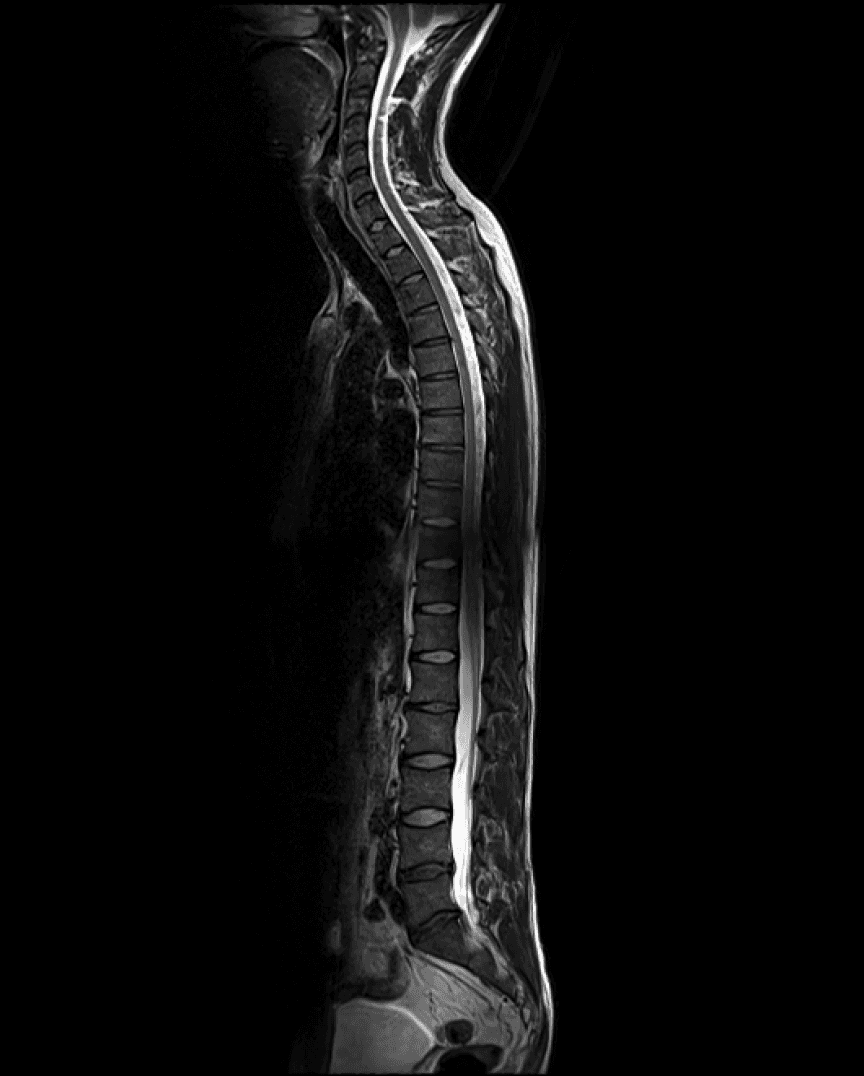

AI-based annotation of your body

Easily understand highly technical scans.